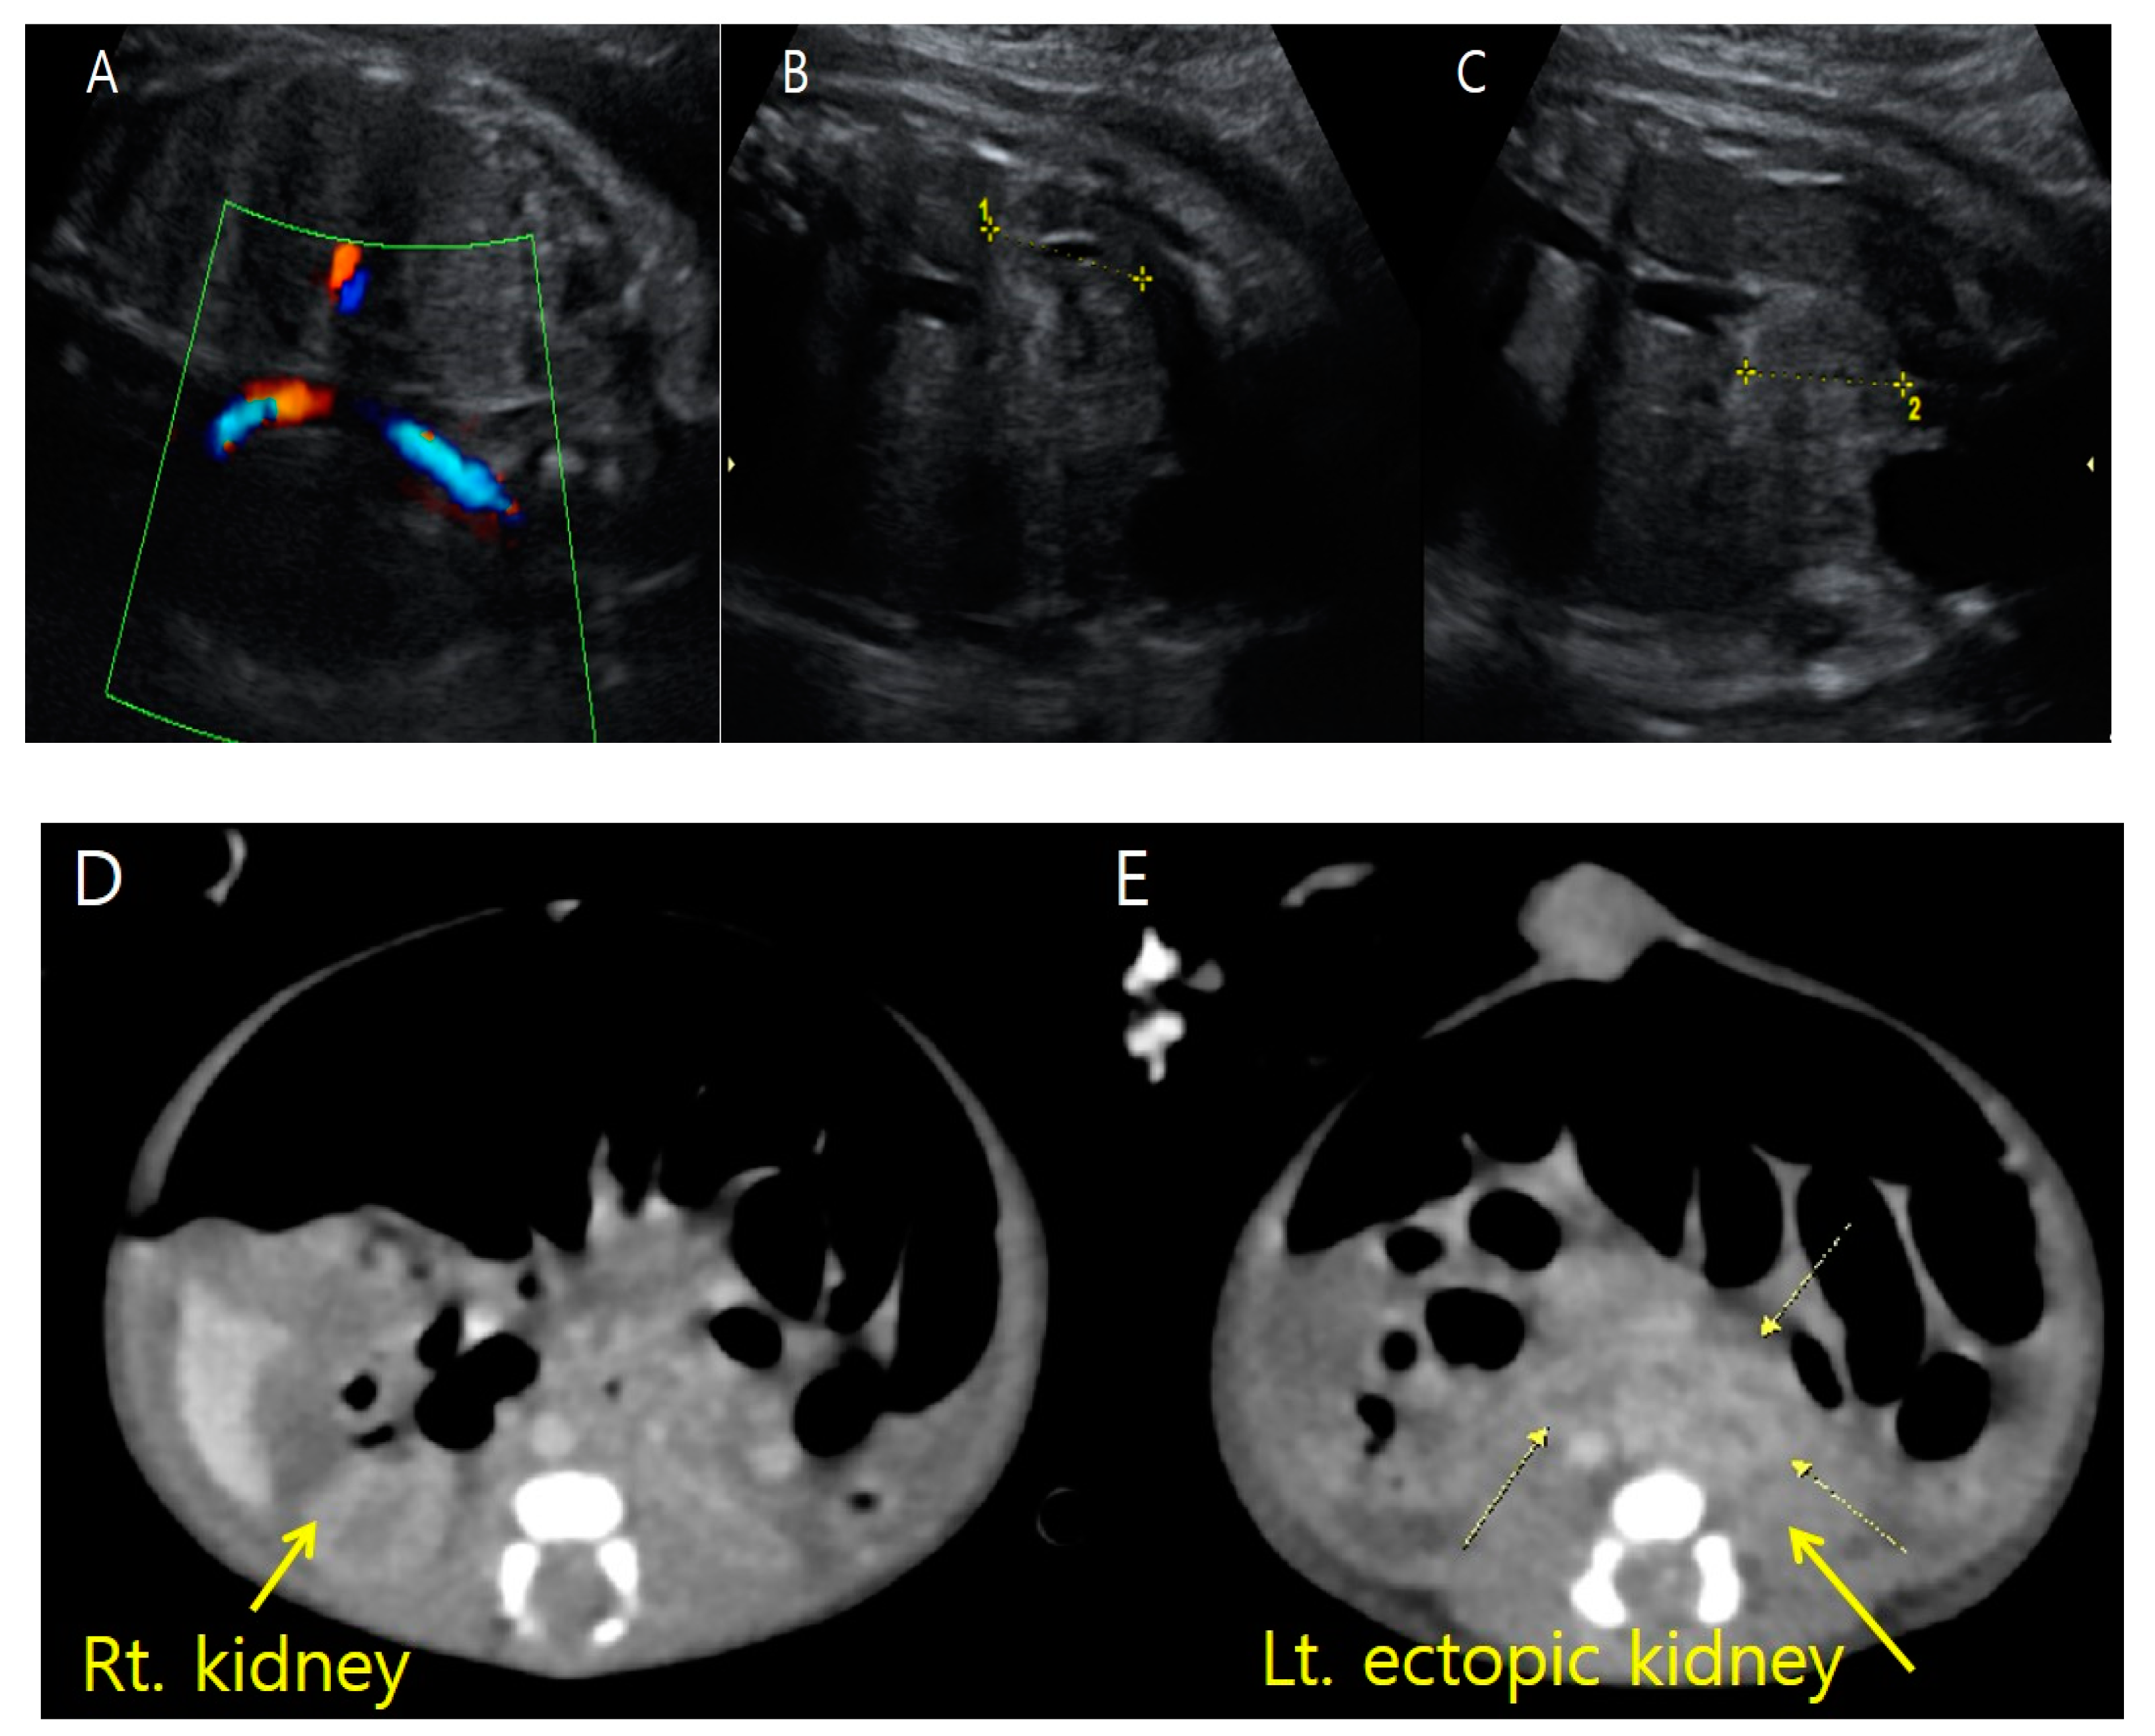

Fetus A’s right kidney was located in the normal renal fossa. Although fetus A’s right kidney was relatively small, it showed normal corticomedullary differentiation without structural abnormalities. On coronal view exams using color Doppler ultrasonography, we found only the right renal artery originating from the descending aorta. To rule out unilateral renal agenesis, we scrutinized the entire pelvic area and finally found the left kidney. However, the left kidney was also relatively small and displaced to an ectopic site almost adjacent to the bladder and near the midline of the body (Figure 4). A single umbilical artery was observed in fetus A (Figure 5).

Figure 4. Prenatal ultrasonography at 31 + 1 weeks gestation and postnatal abdominal three-dimensional computed tomography show fetus A’s ectopic left kidney. (A) On color Doppler ultrasonography, there was no definite renal flow to the left usual renal fossa. (B) Fetus A’s right kidney is relatively small (2.26 cm in length) but located in the usual position. (C) Fetus A’s ectopic left kidney is also relatively small (2.27 cm in length) and located almost adjacent to the bladder. (D) The right kidney is in the regular position. (E) The ectopic left kidney lies adjacent to the bladder and anterior to the spine.